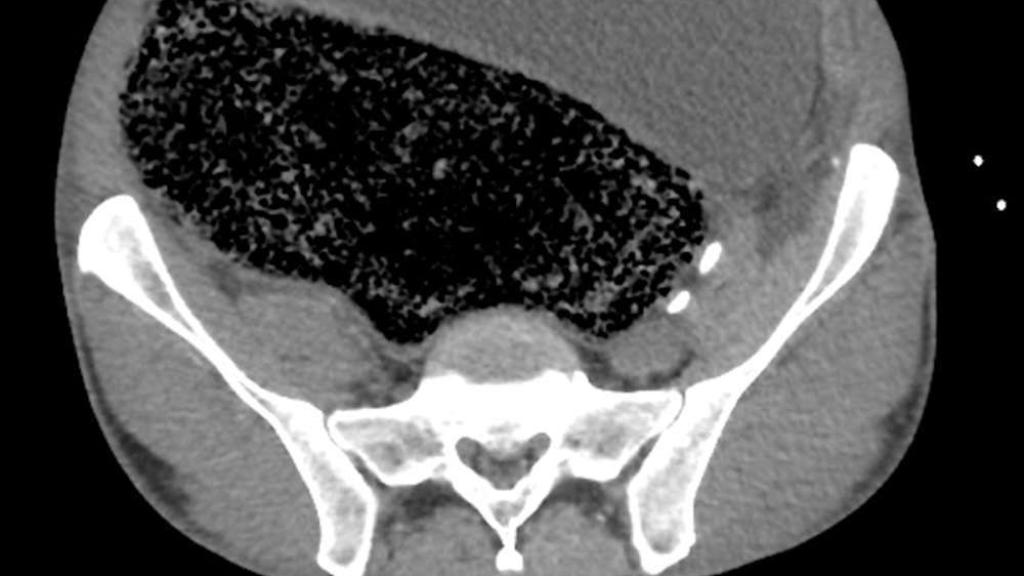

Imagen por escáner de la impactación fecal masiva que sufría el paciente en su abdomen. BMJ Case Reports

Lo que vemos en la imagen del interior del cuerpo del paciente que ilustra este artículo no es un órgano inflamado, el crecimiento de un tumor masivo o un cuerpo extraño a su propio organismo. Es caca. Por motivos que no han trascendido, este australiano de 57 años llevaba días sin ir al baño. Pero no acudió finalmente al médico hasta que se presentó un síntoma alarmante: había perdido el uso de la pierna derecha.

El paciente no tenía un historial de enfermedades cardiovasculares ni de medicación o consumo de estupefacientes que justificasen el diagnóstico de isquemia, el corte del riego sanguíneo que proporciona la arteria a la pierna. Fue el escáner abdominal lo que reveló un caso extremo de impactación fecal, la situación en la que las heces retenidas se endurecen y secan en el interior del organismo, formando una gran masa.

En este caso, la compactación había llegado al punto de provocar la distensión de su intestino grueso y abdomen, y la enorme masa impactada presionaba contra su arteria ilíaca derecha, provocando la isquemia responsable de cortar el riego a su pierna. También sufría síntomas de fallo renal y acidosis metabólica -una acumulación perniciosa de ácido- que determinaron una intervención quirúrgica inmediata.